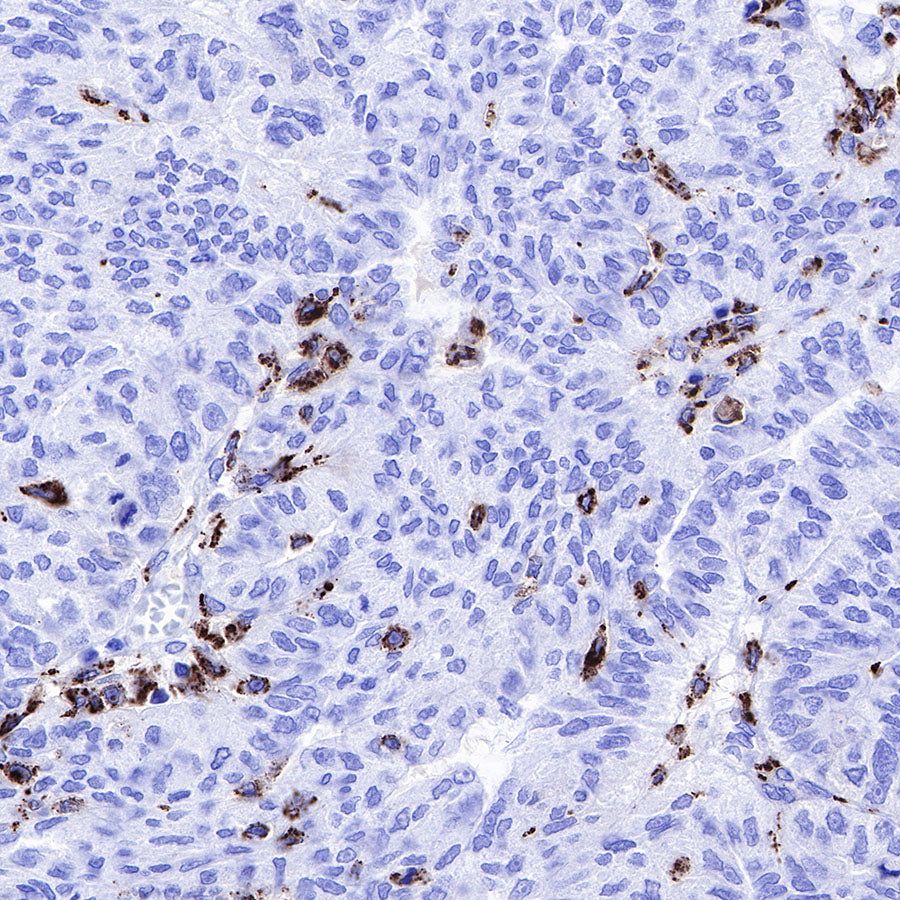

IHC shows positive staining in paraffin-embedded human ovarian carcinoma. Anti-CD68 antibody was used at 1/1000 dilution, followed by a HRP Polymer for Mouse & Rabbit IgG (ready to use). Counterstained with hematoxylin. Heat mediated antigen retrieval with Tris/EDTA buffer pH9.0 was performed before commencing with IHC staining protocol.